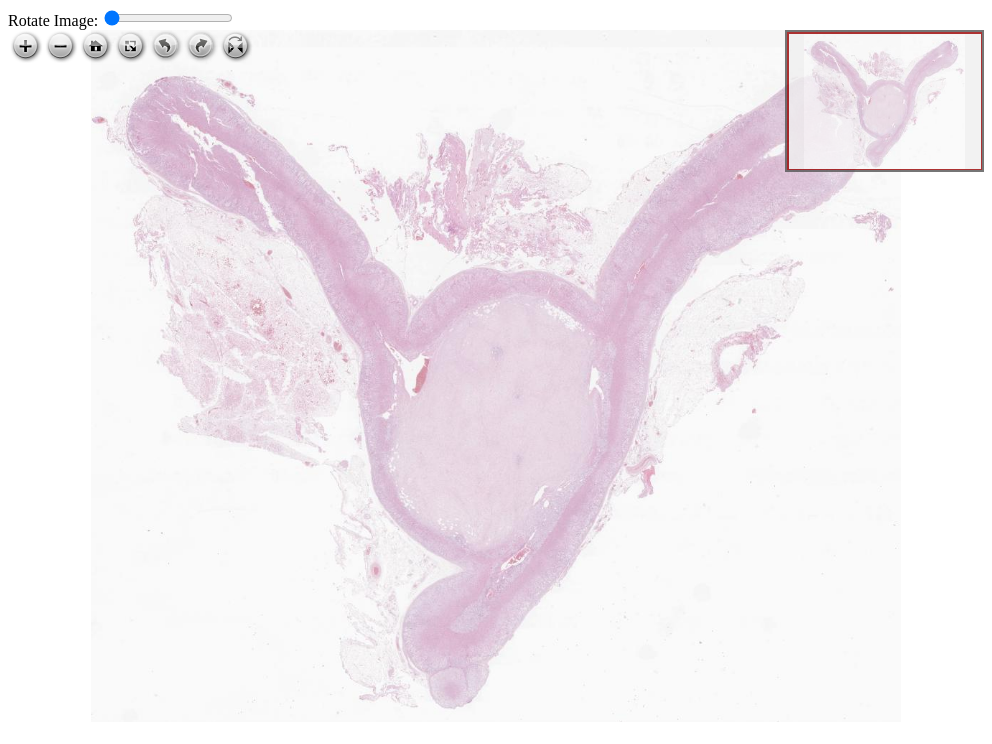

Ganglioneuroma in adrenal gland